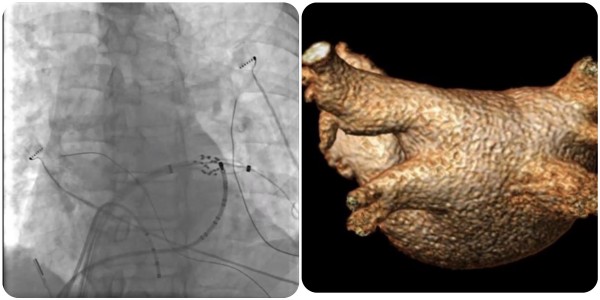

近日,捆绑调教 (简称捆绑调教 )心血管内科团队完成广西首批三维标测系统指导下经皮导管脉冲电场消融术(即CardiPulse脉冲电场消融系统上市后广西首批应用),为一名阵发性房颤患者进行了房颤脉冲电场消融治疗,成功帮助患者恢复正常心律。

在夏文豪的指导下,捆绑调教 心血管内科心律失常介入团队为患者制定了个性化诊疗方案,并联系介入导管中心、重症医学科、心胸外科、手术麻醉中心做好应急预案,为手术全程保驾护航。手术仅2小时,消融过程中患者心律转为正常,肺静脉即刻隔离,术后恢复良好,目前已康复出院。

脉冲电场消融(Pulsed Field Ablation,PFA)利用短时程、高电压的多个电脉冲释放消融能量,可在细胞膜上产生不可逆的纳米级微孔,导致细胞死亡,可用于房颤导管消融,实现肺静脉隔离。

与其他能源不同,脉冲电场消融应用快速交替的高电场,导致电穿孔和心脏细胞死亡,以非热的方式造成细胞损伤。临床前和人类首次研究表明了相对的组织选择性,证明了对心肌细胞损伤的高效性和周围结构(包括食道、膈神经和脉管系统)的低易损性。